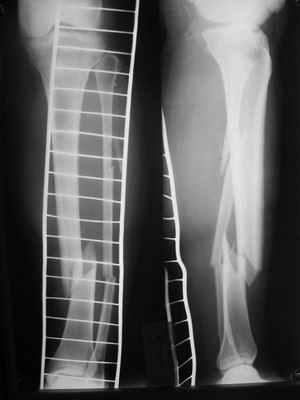

Здравствуйте уважаемые коллеги. Позвольте поделиться опытом применения интрамедуллярного остеосинтеза большеберцовой кости имплантатами компании ?Остеомед" с запатентованной прицельно-навигационной системой для дистального блокирования ?Интерлок". Для определения длинны и диаметра стержня использовали линейку-шаблон, позволяющей с легкостью рассчитать длину и диаметр стержня с проекцинно искаженными размерами, как конечности, так и линейки-шаблона.Дистракцию производили с помощью спицевого дистрактора с последующей закрытой репозицией отломков винтами Шанца. Все основные этапы производили по методике АО, гарантированное дистальное блокирование достигается за счет центрирования отверстий, путем контролирования смещения стержня в костномозговом канале в сагиттальной плоскости. Клинический пример:Больная Я. 45 лет, пострадала в результате случайного падения на улице 19.12.2005., имеет место открытый 1 степени перелом обеих костей левой голени со смещением отломков.произведена закрытая репозиция перелома с последующим введением стержня (на данном этапе производился рентген-контроль)Убедившись в достаточной репозиции перелома, произведено дистальное и проксимальное блокирование интрамедуллярного стержня.Общее время затраченное на оперативное вмешательство составило 45 минут.